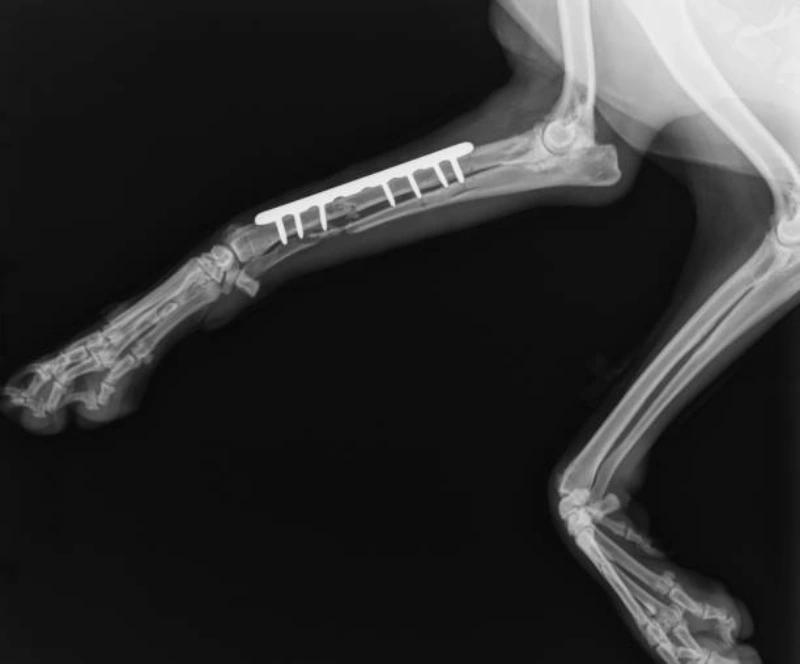

Esse exame permite identificar problemas como fraturas, tumores, alterações cardíacas e respiratórias, fornecendo informações cruciais para o diagnóstico e tratamento adequado.

Esse recurso permite visualizar ossos, órgãos e tecidos de forma não invasiva, auxiliando no diagnóstico de fraturas, tumores, alterações cardíacas e problemas respiratórios.